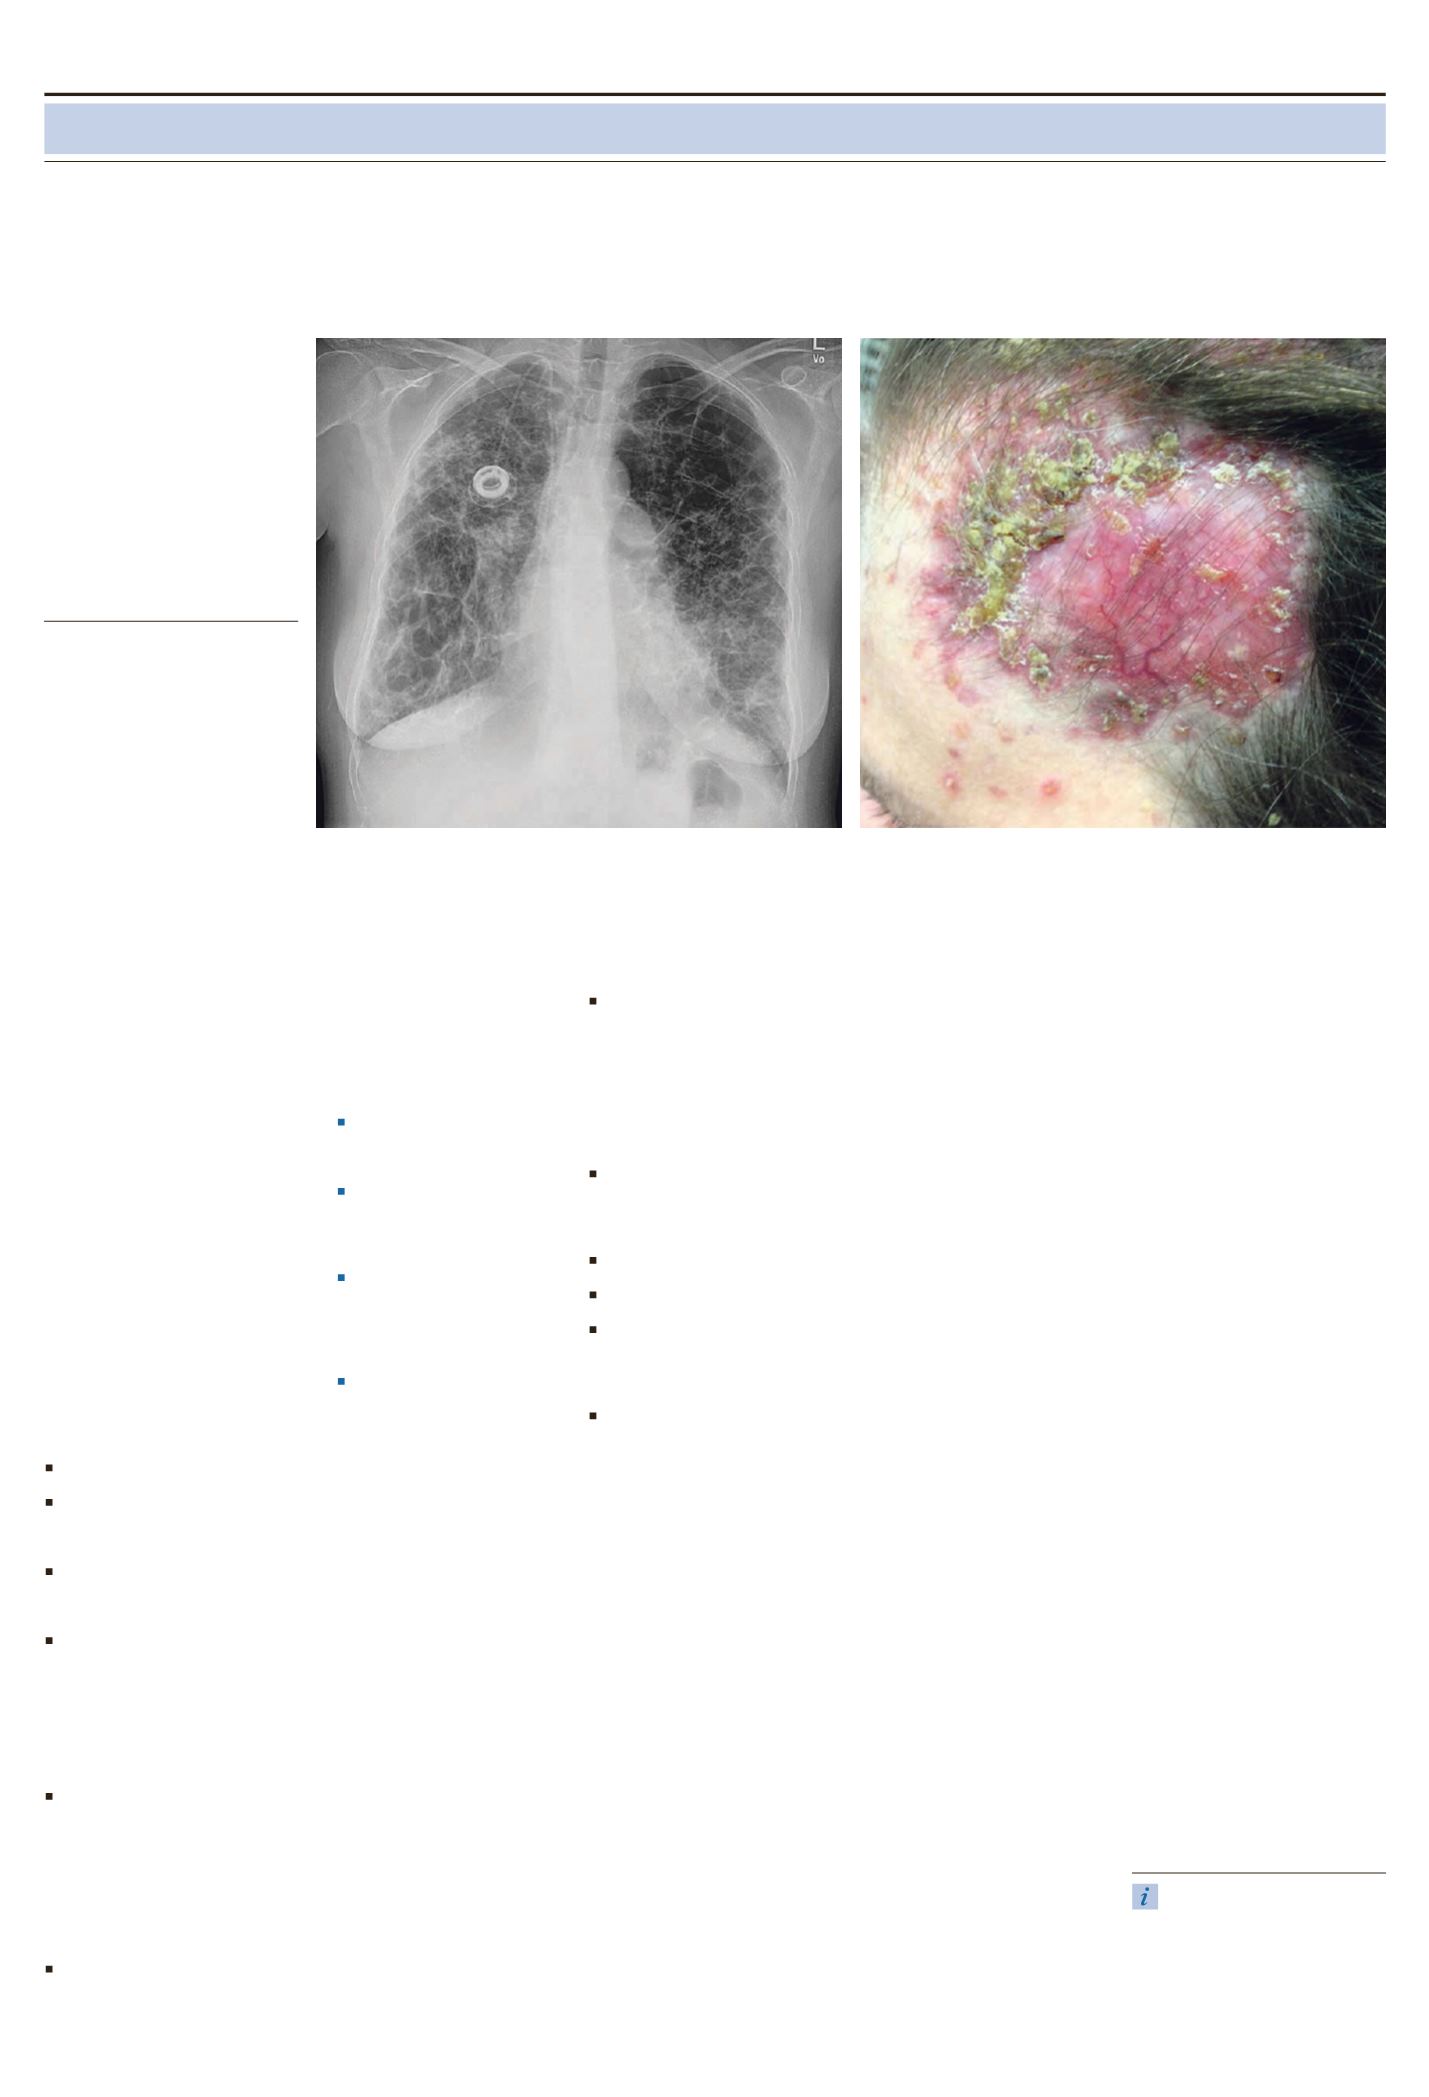

Die Patientin befand sich in einem re

duzierten Allgemeinzustand und un

auffälligen Ernährungszustand. Sie

war tachypnoisch. Am Kopf waren

scharf begrenzte plattenartig indurier

te entzündliche Hautveränderungen

zu erkennen (siehe Abbildung). Inner

halb dieser bis zu 10 cm durchmessen

den Plaques manifestierten sich neben

Pusteln vereinzelt auch eitrige ulzerie

rende Knoten an der frontalen Halsre

gion, am Unterbauch und in der Geni

talregion. Keine Ödeme. Pulmohyper

Röntgenthorax: Ausgeprägte fibroti

sche Veränderungen der Lungenmit

telund unterfelder beidseits sowie

der Oberfelder rechts mehr als links.

Weitere bullös emphysematische Ver

änderungen auch in den übrigen Lun

genabschnitten. Normale Herzgröße.

Pulmonalissegment prominent.

Schmales u. mittelständiges oberes

Mediastinum (siehe Abbildung).

Röntgenthorax.

Scharfbegrenzte plattenartig indurierte entzündliche Hautveränderungen (bis zu 10 cm)

auf dem Kopf der Patientin.